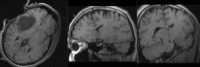

Three registration approaches evaluated: (NiftyReg), (BrainsFit), (SIFT Landmarks).

- Registration of difficult brain images is successful, body images remain challenging.

- Masking of problematic image regions, e.g. pathology, is an important but time-consuming pre-processing task that could be further investigated or automated. For instance, interactive masking/segmentation of pathology, linking registration and masking.

- Registration direction has an important impact, i.e. which images are designed as fixed or moving. Symmetric or bi-directional registration is helpful.